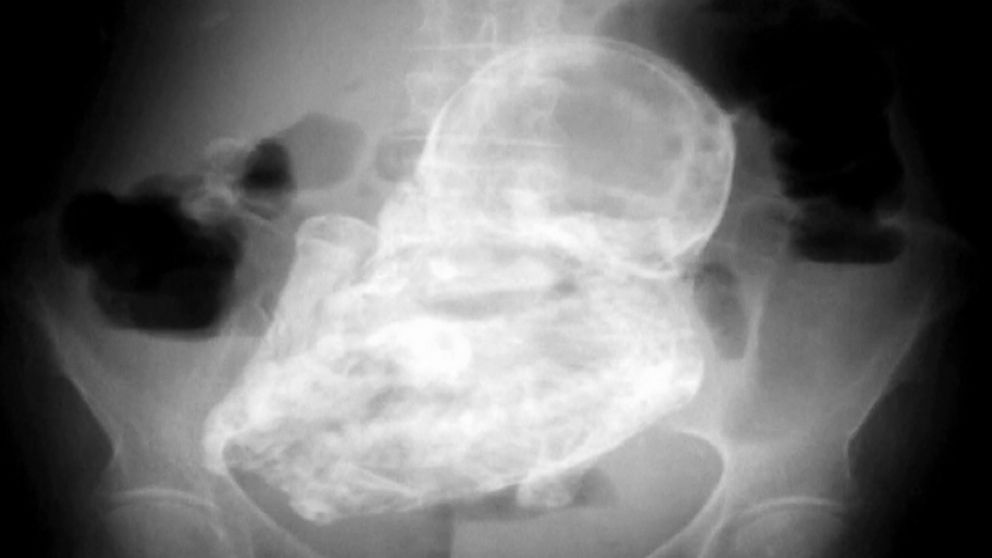

Doctors only discovered the rare medical phenomenon after ordering an X-ray that revealed the lithopedion, also called a “stone baby.” The woman is now expected to undergo surgery to remove it.

Garcsi, who did not treat the Colombian woman, says the lithopedion is created when a pregnancy forms in the abdomen rather than in the uterus. When the pregnancy ultimately fails, usually because the fetus does not have enough blood supply, there is no way for the body to expel the fetus.

As a result, the body turns the fetus to “stone,” using the same immune process that protects the body from any foreign object detected in a person’s system. Garcsi said it may seem odd, but that the process is used constantly in the body to stay healthy.